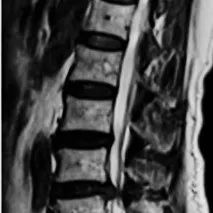

脊柱矢状位序列与中国老年人群腰椎间盘突出的关系

背景腰椎间盘突出( lumbar disc herniation,LDH)是一种常见的的老年退行性疾病。随着年龄的增长,骨骼肌肉的变化及长期的外力会导致脊柱和骨盆形态结构发生变化。不同人群在保持直立姿势时,脊柱矢状位排列不同,这可能导致椎间盘的生物力学发生改变,加速椎间盘退变。作者调查了中国老年人群中不同Roussouly类型的间盘退变程度、突出部位及数量,以明确其关系。方法收集正常人及腰椎间盘患者的资料并分为两组,按照以下纳入排除标准,无症状组212例,腰椎间盘突出症组213例。...